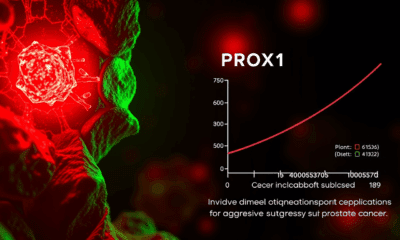

Researchers have identified a gene that plays a key role in prostate cancer cells that have transitioned to a more aggressive, treatment-resistant form. The gene can...